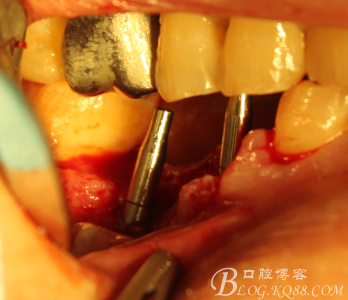

手術全程

翻瓣,拔除C5,跟尖端有吸收

徹底搔刮肉芽,定點,正對顎尖,擴孔同期行慢轉收集自體骨

植入植體

C6頰側填入自體骨,嚴密縫合關閉創(chuàng)口